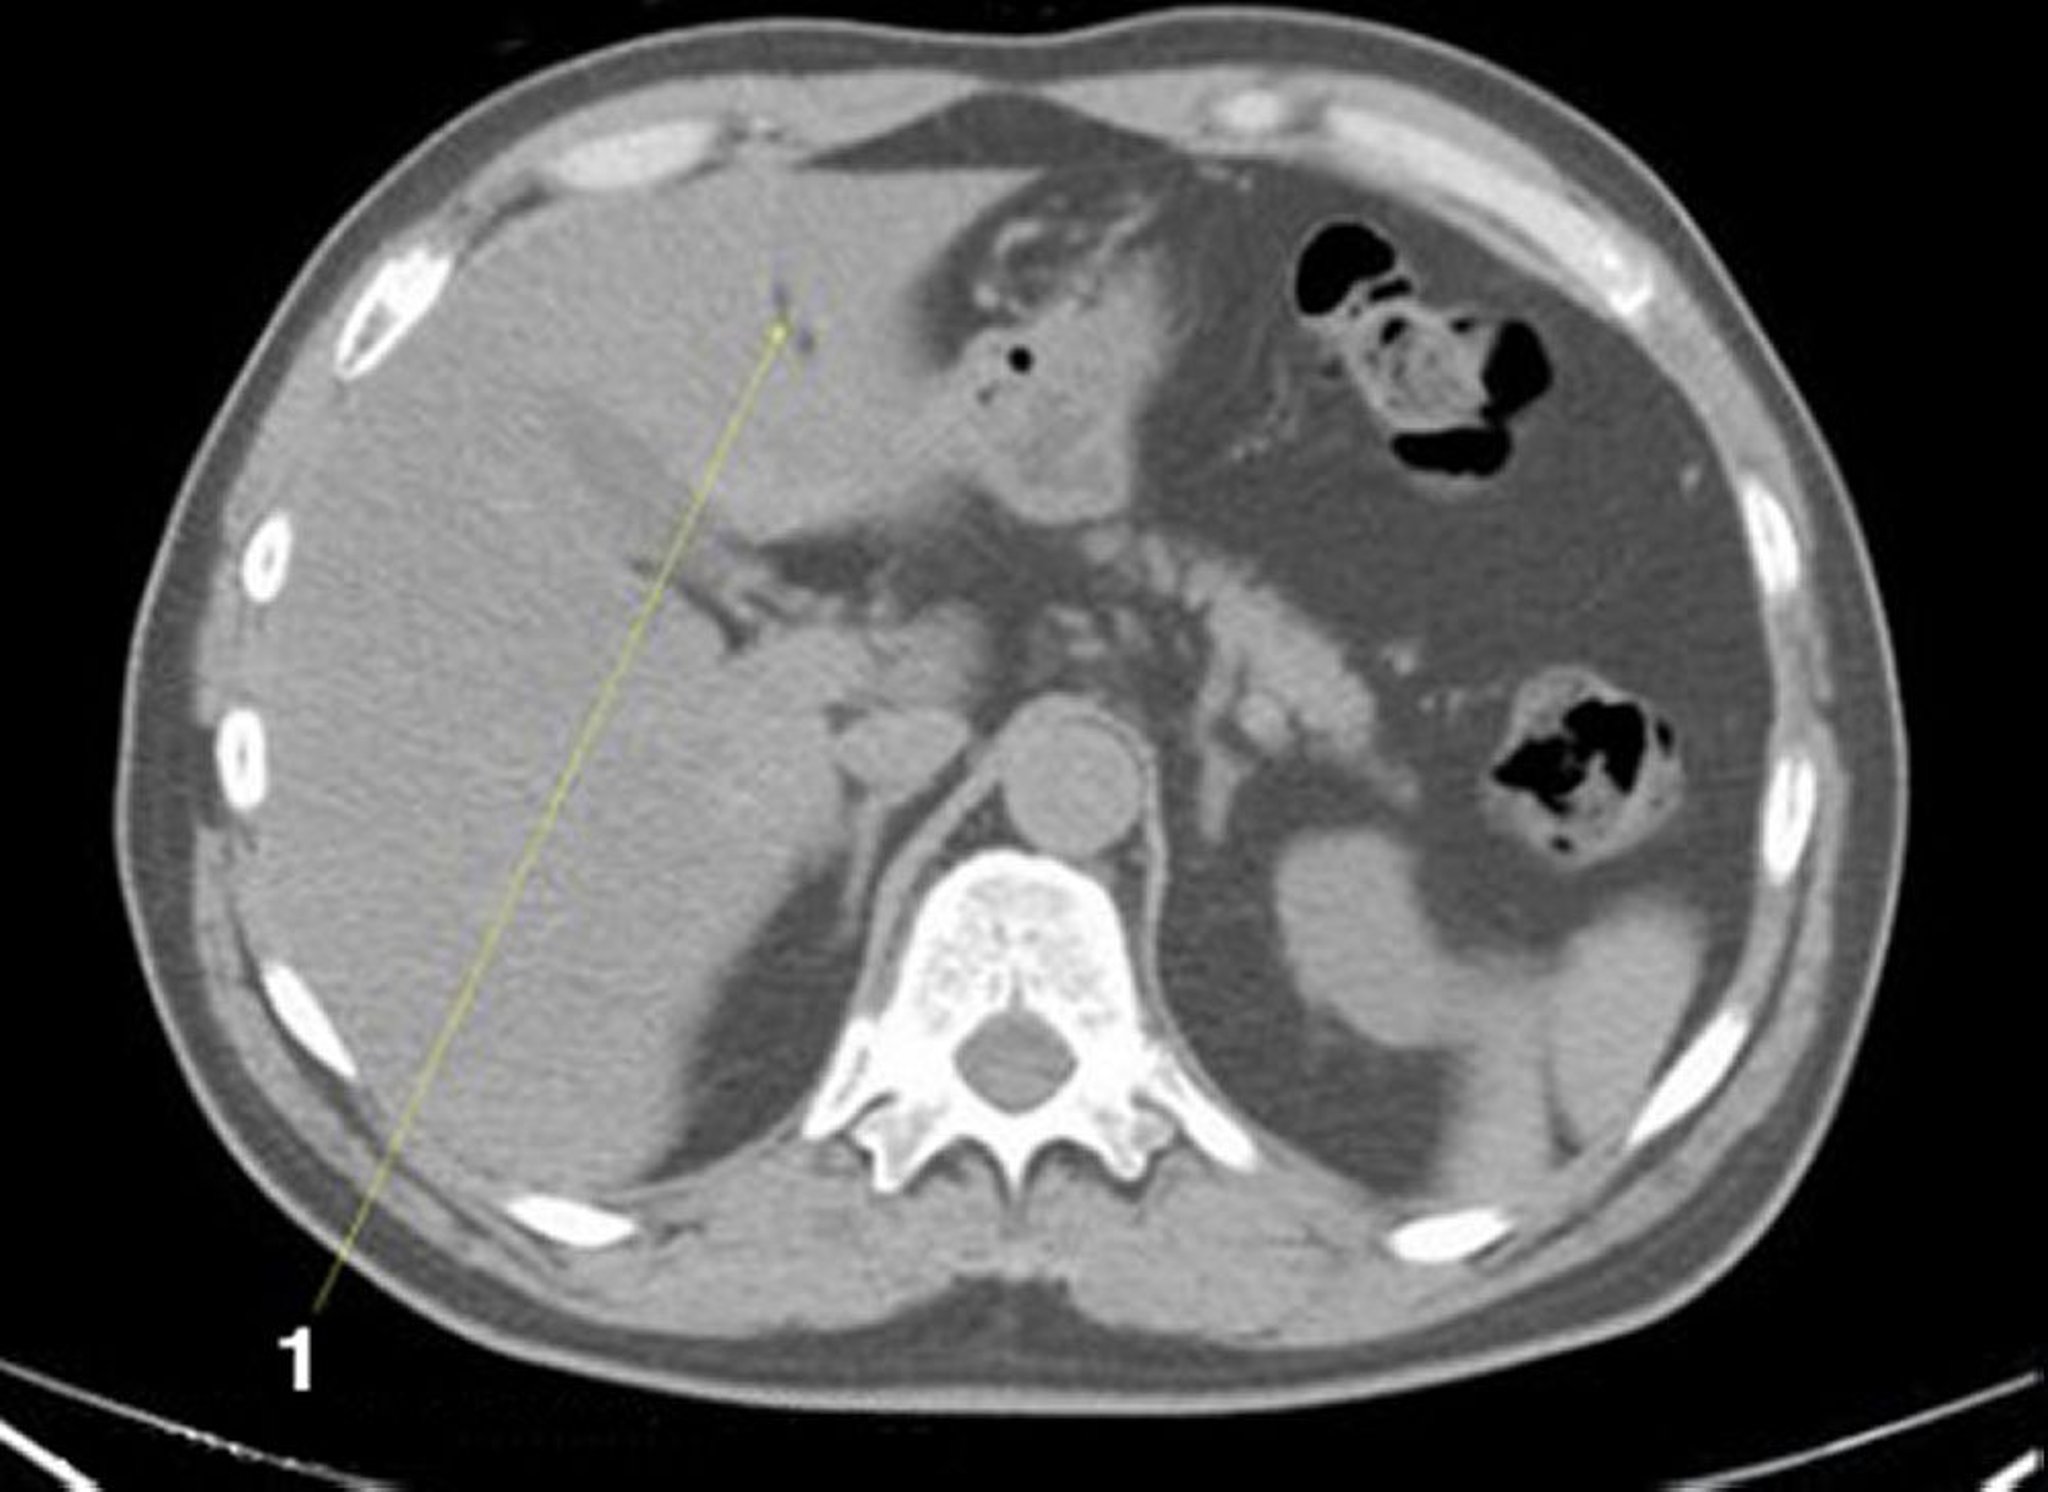

Phim chụp CT vùng bụng và vùng chậu không thuốc cản quang cho thấy giải phẫu bình thường (lát cắt 5)

1 = khe nứt ở dây chằng tròn của xương đùi.